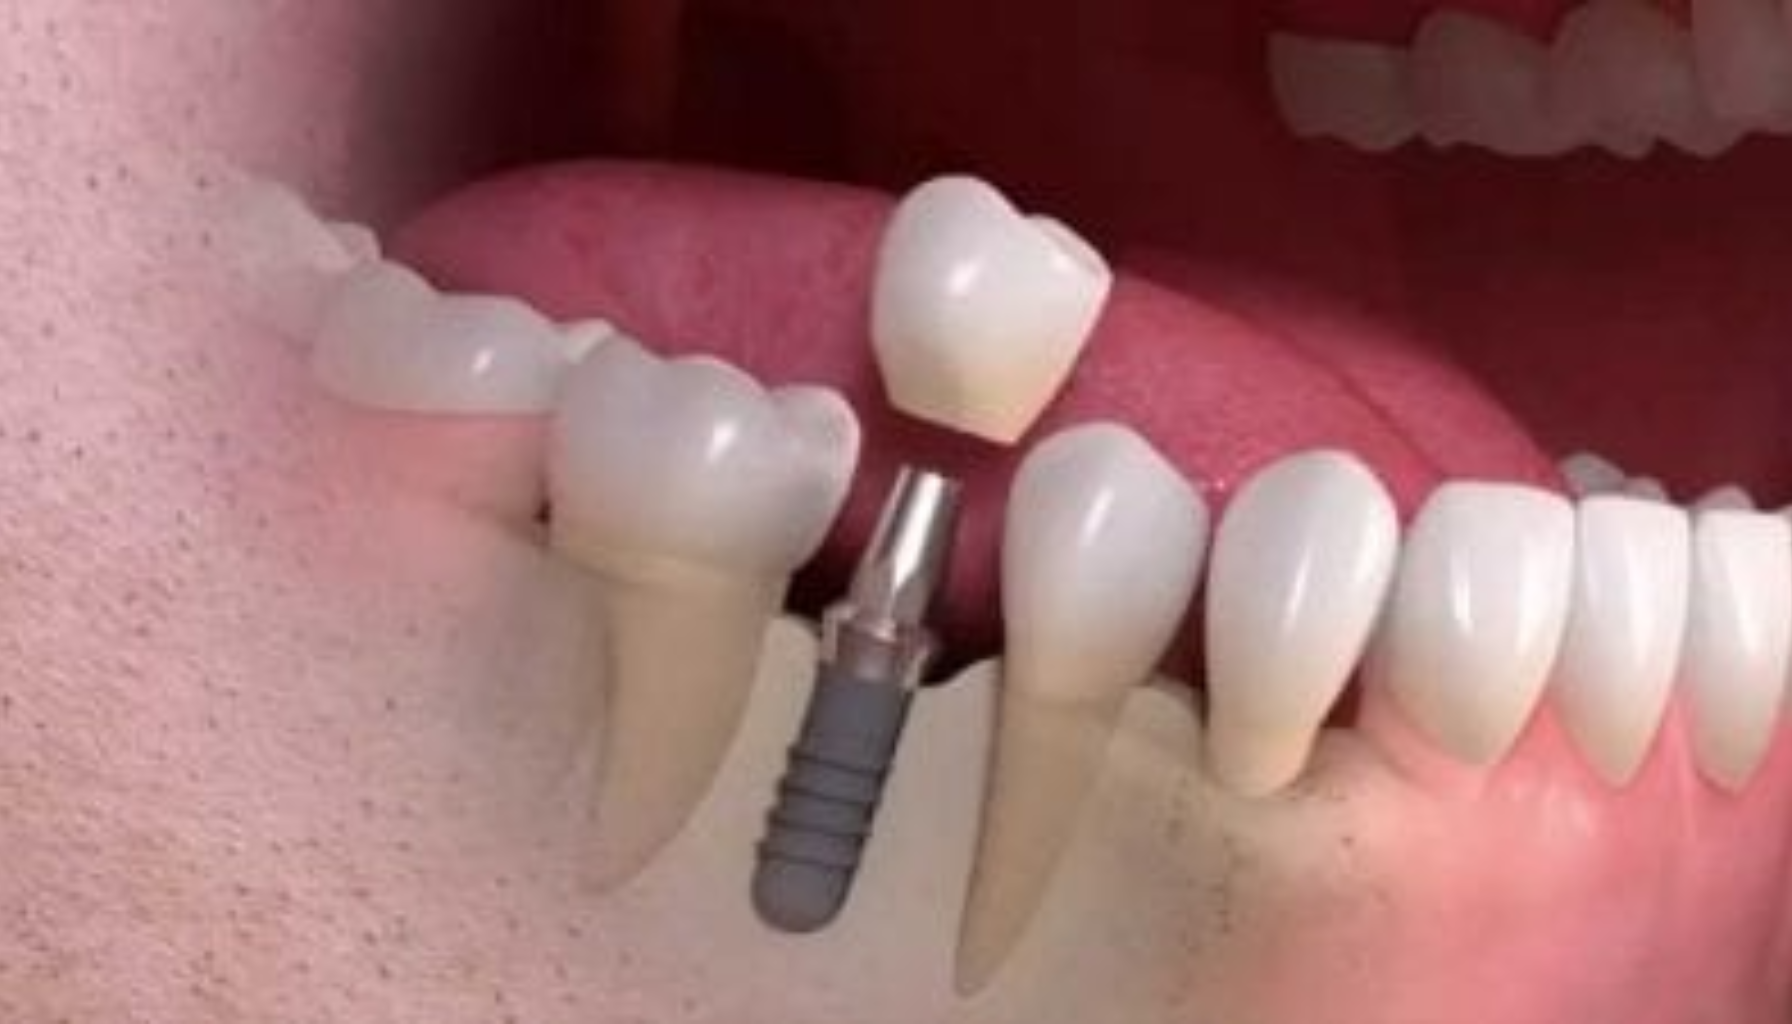

Når rotkanalen er forberedt, plasseres en stift, som vanligvis er laget av metall eller fiber, inn i rotkanalen. Denne stiften fungerer som et fundament for kronen. Etter at stiften er på plass, formes og justeres tannen for å gjøre plass til kronen. Kronen, som kan være laget av porselen, keramikk eller metall, plasseres deretter over stiften for å gi tannen en naturlig form og styrke.

Etter at stiften er på plass, lages det en krone – ofte av keramikk eller porselen – som både ser ut og kjennes ut som en ekte tann. - Fordeler med tann på stift:

Behandlingen er trygg og gir gode resultater, men det er en viss risiko for at tannen kan løsne eller knekke, spesielt hvis lite tannsubstans er igjen. En grundig vurdering hos tannlegen er viktig for å avgjøre om dette er riktig, eller om et tannimplantat bør vurderes.